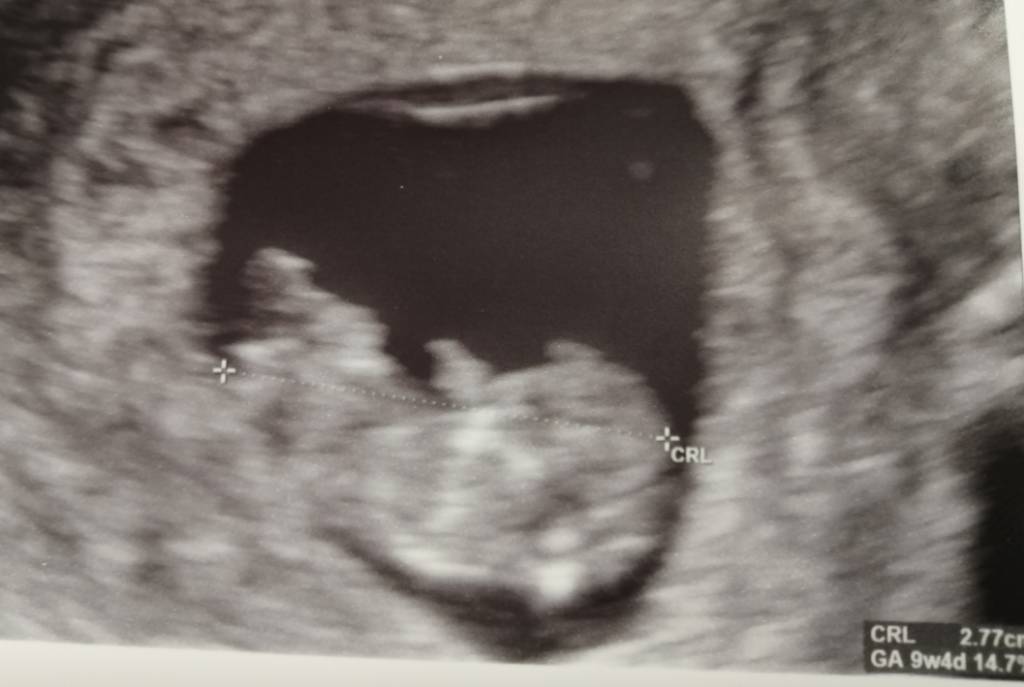

Z maluszkiem wszystko ok, rusza się i to jest najpiękniejsze, co w życiu widziałam [emoji7] już taki mały człowieczek, ma rączki, nóżki, no wszystko żeby wyglądać jak człowiek [emoji16] serduszko 178, lekarz mówił, że ok. No i ma już 2,8 cm [emoji3590] na zdjęciu tak korzystnie nie wypadło, ale na usg na żywo to jest boskie [emoji3059]

Następna wizyta 08.10, to będą prenatalne. Mam zrobić tydzień wcześniej pappa [emoji6]

No i na usg już tylko 2 dni różnicy z om, więc będę posługiwać się om. Jutro zaczynam 11 tydzień [emoji3590]